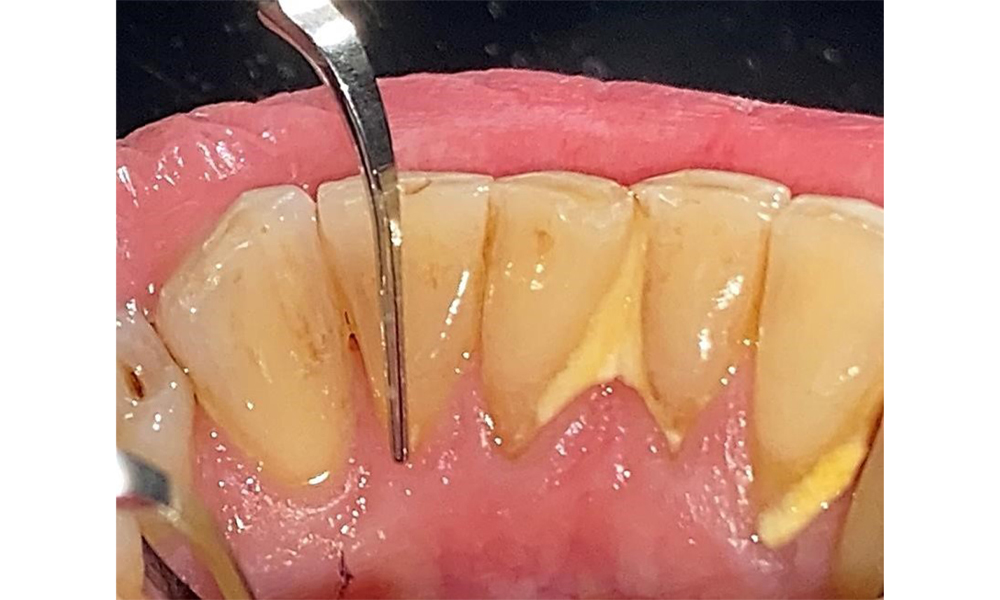

Der Patient hat eine Parodontitis Stadium II, Grad B (5). Die klinischen Sondierungstiefen liegen mit 1-3mm im physiologischen Bereich. Lokalisierte Sondierungstiefen finden sich an 17 und 27 jeweils mesiopalatinal mit 5mm. Es liegen generalisierte Rezessionen von 1-3mm vor mit partiellem Verlust der Interdentalpapillen (Abb. 2, Abb. 3, Abb. 4)

Der Patient pflegt mit Interdentalbürstchen und mit einer elektrischen Zahnbürste. Er zeigt eine gute Compliance und ein gutes häusliches Mundhygieneverhalten bzw. - verständnis. Eine regelmäßige Motivation und Reinstruktion sind aufgrund des Progressionsrisikos unerlässlich insbesondere der Interdentalraumpflege aufgrund der erhöhten Sondierungstiefen in diesen Bereichen. Es zeigen sich lokalisiert Zahnstein in der Unterkieferfront lingual und weiche Beläge, die dem Patienten aufzuzeigen sind. Ggf. müssen Interdentalbürstchen auf die Größe geprüft und angepasst werden. Ein weicher Bürstenaufsatz ist aufgrund der freiliegenden Wurzeloberfläche zu empfehlen, um keilförmigen Defekten vorzubeugen. Eine Zahnpasta mit einem niedrig abrasiven Wert sollte angewendet werden.

In der Instrumentierung sind bezüglich der Methodenwahl keine Einschränkungen gegeben. Aufgrund der parodontalen Vorerkrankung und dem hohen Rezidivrisikos ist die Vorbeugung einer Erkrankungsprogression durch die regelmäßige supra- und subgingivale Instrumentierung unerlässlich. Die Wahl der Instrumente zur mechanischen Biofilmentfernung ist aus allgemeingesundheitlicher Sicht nicht eingeschränkt und erfolgt bedarfsgerecht. Harte und mineralisierte Beläge wie Zahnstein und Konkremente sind mittels Handinstrumenten oder Schall/ Ultraschallscalern zu entfernen (Abb. 9) (8, 9).